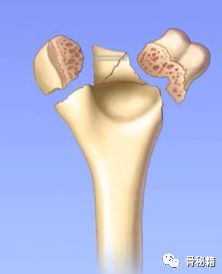

说到复位的细节,就要了解肱骨远端的解剖

1.解剖中比较重要的就是柱的概念,分为外侧柱和内侧柱,一个重要的滑车结构包含了300度的关节面,在外侧有一个肱骨小头的结构,然后一个冠突窝的结构

2.其中有几个重要的角度,4-8度的轻微外翻角,30度前方的前倾角

肱骨的内外侧柱和滑车构成了一个三角形稳定结构,手术复位的时候一定要完成稳定三角结构的恢复。

肱骨远端复位原则:先柱还是先关节面?

理论上是滑车first!有的时候也可以先复位简单的。先复位滑车,是功能保证,那300度的关节面的复位需要达到解剖,加压!然后再进行柱的复位